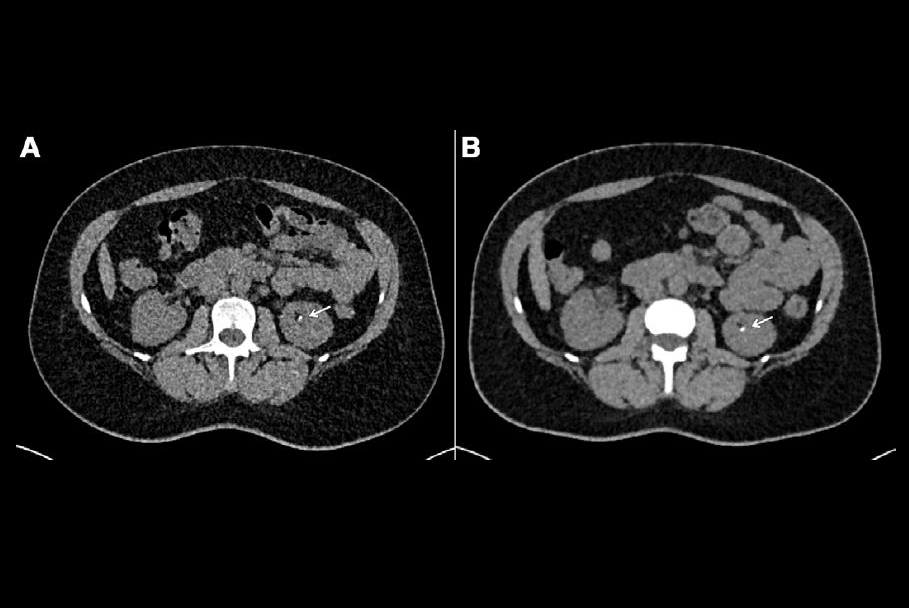

Examples of native T1 and T2 mapping in the reference group and renal mass cohorts with region of interest (ROI) delineation. A: Native T1 mapping (left) and T2 mapping (right) coronal raw images of normal kidneys. Three oval ROIs measuring 0.30cm2 were manually drawn at the same symmetrical location of the left and right kidneys, including the superior, middle, and inferior pole of the cortex. B: Native T1 mapping (left) and T2 mapping (right) coronal image of an oncocytoma of the upper pole of the right kidney (maximum diameter: 3 cm). A freehand circular ROI in the tissue part of the mass was set at 1.0cm2.Images courtesy of Dr. Remy Henry, Prof. Catherine Roy, et al, and European Journal of Radiology.

The group recorded the renal cortex values of 125 patients with normal kidneys (reference group) and 75 patients with renal masses on a clinical 3-tesla MRI unit (Ingenia CX, Philips) and a standard 32-channel torso phased-array coil using T1m and T2m sequences. For the quantitative evaluation, measurements were performed by delineating regions of interest (ROIs) on T1m and T2m sequences in the renal cortex of the reference group and in renal masses.